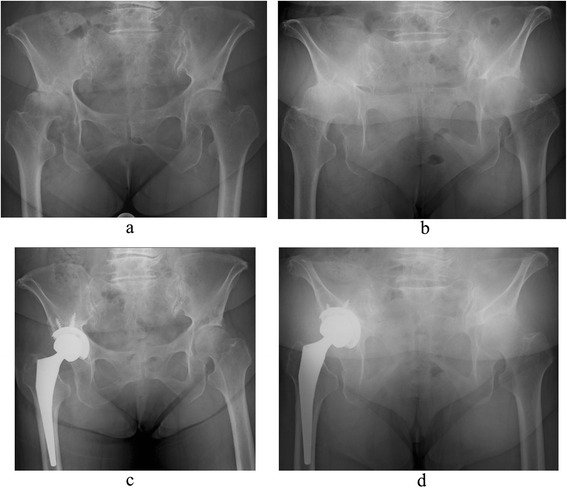

Fig. 1.

A 64-year-old woman with left hip osteoarthritis (after total hip arthroplasty). Anteroposterior pelvic radiographs taken after left total hip arthroplasty (THA) are shown. In the supine position (a), cup inclination is 45°, and cup anteversion is 25°. However, in the standing position, the pelvis markedly tilts backward; cup inclination is 59°, and cup anteversion is 42° (b). Although this case is not included in the present study, the case, in which the hip joint was anteriorly dislocated 2 weeks after THA (c), triggered the initiation of the study